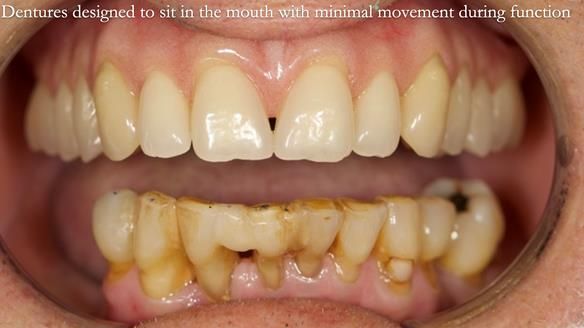

Welcome to my Newsletter 54 showing the making and fitting of dentures (a complete upper metal reinforced denture, a lower immediate partial denture and a definitive Scandinavian designed, metal based lower partial denture) for David, a 75 -year-old man. The full protocol workflow is presented including the use of dentate photographs to mimic his natural teeth.

Interestingly we found that the upper complete denture when finished and fitted didn’t have good enough retention for David’s satisfaction. It was relined by adding compound to the buccal flanges – to almost overextend into the sulcus to ‘create’ a sulcus, followed by using a light bodied silicone impression material. This improved the function of the C/-considerably. A lower Scandinavian hygienically designed lower RPD was also provided which helped with occlusal stability and reseating the upper denture – further improving the fit.